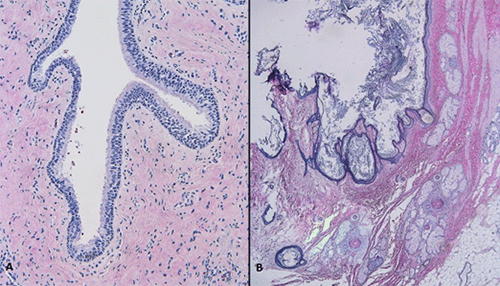

Figure 5. Microscopic Findings Consistent with Teratoma. Published with Permission

A, Respiratory epithelium and dense fibroconnective tissue; B, skin with adnexal structures, including hair follicles, keratin debris, pilosebaceous units, smooth muscle, and adipose tissue

Surgical resection specimens consisted of a 30 cm intact, red cystic structure with smooth external surface, weighing 18 pounds (Figure 4A), as well as a 2 cm intact mass with similar morphologic features, weighing 8 grams. Sectioning of the specimen revealed a unilocular cyst filled with greasy, yellow-gray granular material admixed with hairs, friable keratin-rich debris, and adipose tissue (Figure 4B). Histologic sections demonstrated a mature teratoma with elements from all three germinal layers: endoderm (Figure 5A), ectoderm (Figure 5B), and mesoderm (Figure 5B). No immature elements were appreciated. Final pathology demonstrated two mature cystic teratomas with the larger measuring 18 pounds, both negative for malignancy. Lymph nodes were similarly negative for malignancy.